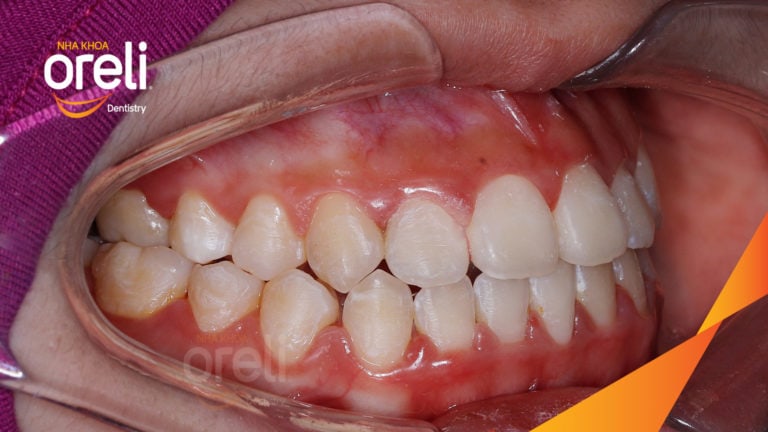

Ca niềng chỉnh chen chúc sai khớp cắn hạng 3 móm nhẹ – Kết quả thực tế ở Oreli Niềng răngChen chúcMóm Xem thêm